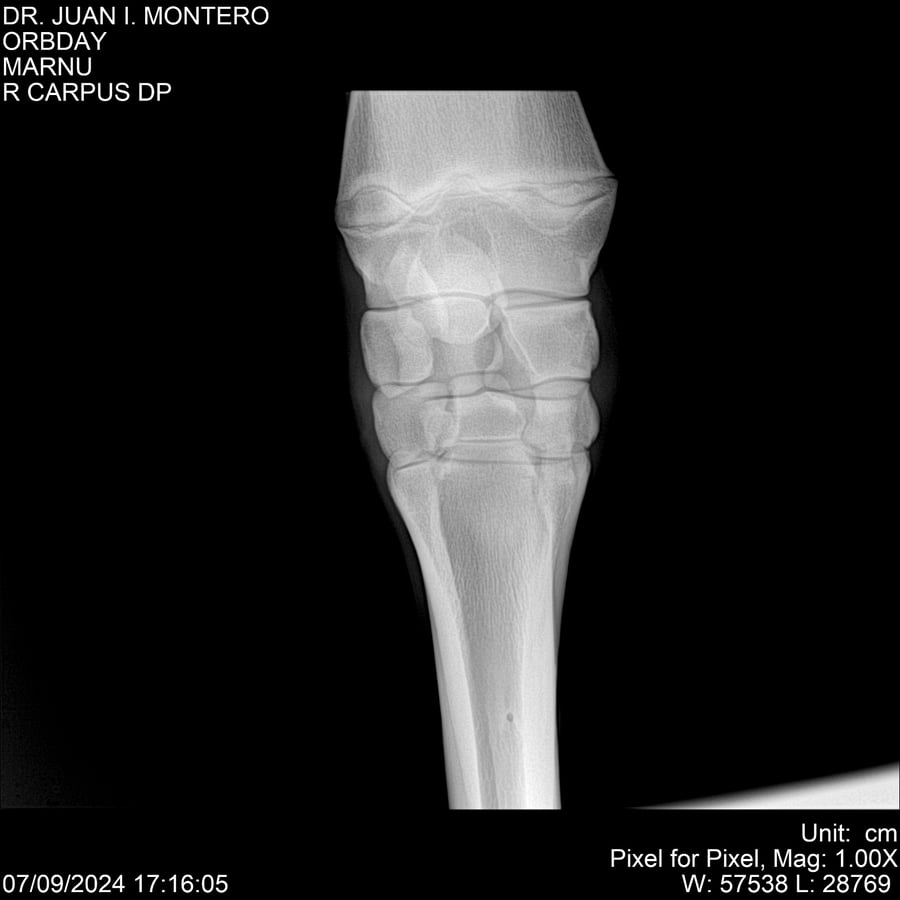

• Empresa: Abelenda N. R., Walter Hugo